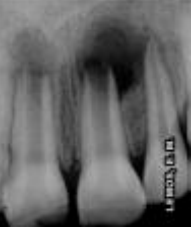

Analisando a imagem radiográfica ao lado, observou-se a presença de lesão periapical nos incisivos superiores. Segundo o relato do caso, a criança sofreu um acidente traumático (queda no toboáguá, batendo a boca no fundo da piscina) há um ano. Clinicamente observou-se uma fratura coronária no dente 11, com envolvendo esmalte, dentina, e no dente 21 fratura de esmalte. Relatou ainda que os dentes ficaram muito moles e que aos poucos a mobilidade cessou. No exame radiográfico observou-se rizogênese incompleta, com presença de lesão em ambos os dentes.

Assinale a alternativa correta quanto ao tratamento corretamente indicados para o paciente e o objetivo do mesmo, respectivamente: